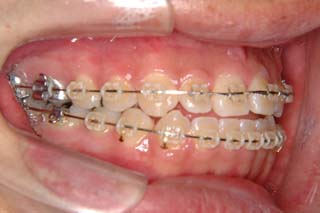

治療期間:動的処置3年2か月、経過観察3年

次第にアゴのズレが取り除かれて、しっくり噛めるかみ合わせに変化していっています。長い年月をかけて修飾されてきた顎関節の環境はなかなか良い形に変わりませんので、時間をかけて改善を行います。